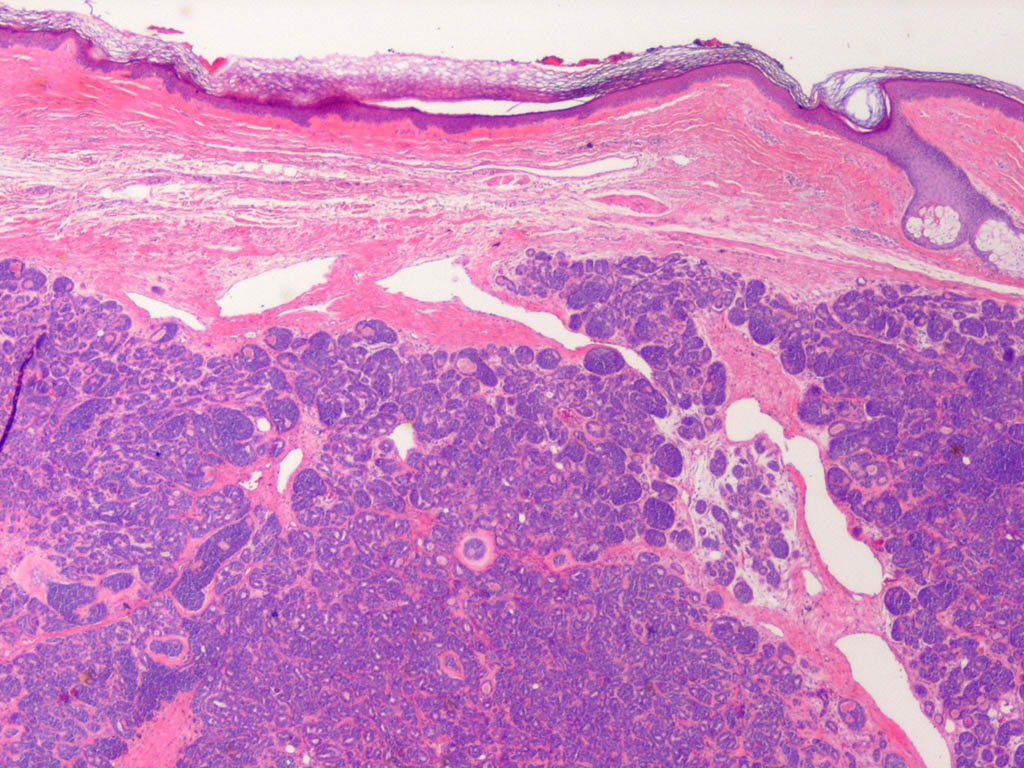

Cylindroma =الأسطوانوم

OLYMPUS DIGITAL CAMERA